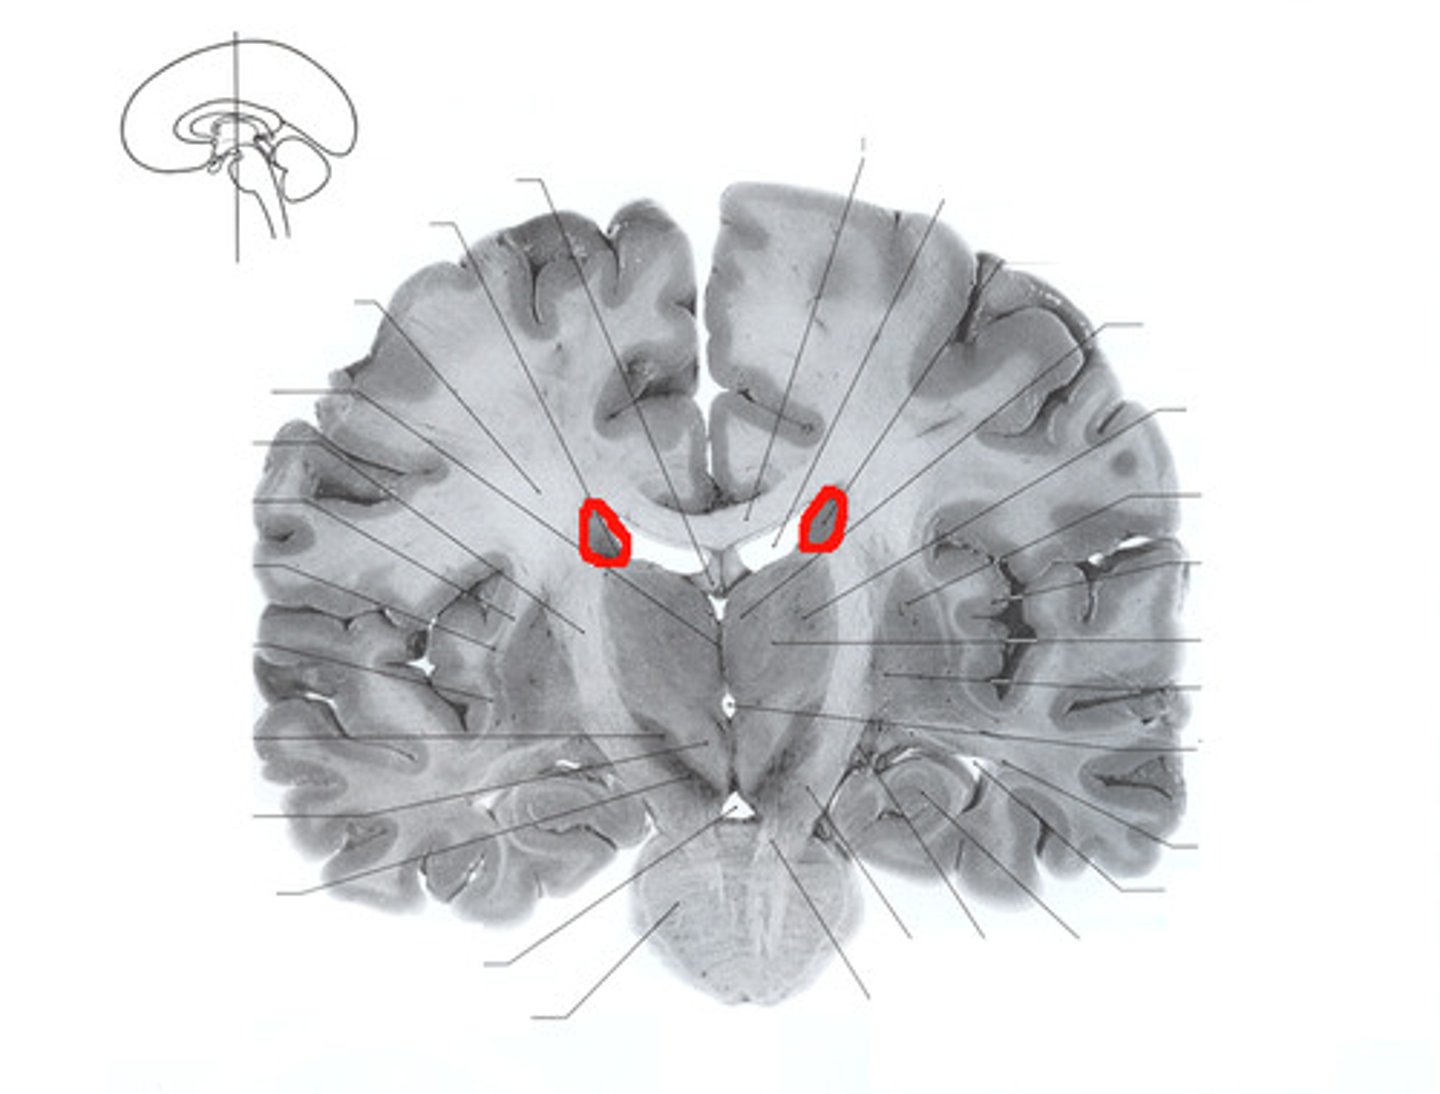

Caudate Nucleus

Globus Pallidus

Putamen